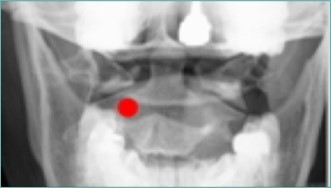

Because of the proximity to the vertebral artery and the potential risk of intravascular injection, few interventionalists have been interested in AA injections, and, since the proximal GON travels over the posterior arch of the atlas, even fewer have been interested in direct injections of the proximal GON. In an effort to avoid the “locked-in” syndrome complication seen with occipital injections, Dr. Gabor Racz developed a suboccipital approach to the suboccipital space in 1982, which has recently become more popular7, 8. A curved, bullet-tipped needle with side port injection, attached tubing, and wings (dubbed the “Stealth needle”™ because of its resemblance to the Stealth bomber) Figure 5 is used to approach the suboccipital triangle from above. Since the underlying pathology is usually bilateral, the procedure is usually performed bilaterally.The patient is positioned prone on the fluoroscopy table, with the neck in flexion; the hair is pulled cephalad, and the suboccipital area is sterilely prepped and draped. The inion and conjoined tendon are identified by palpation and the nuchal line is identified by fluoroscopy; the entry site should be 2cm lateral to the midline on the nuchal ridge. After making sure by palpation that the planned entry is not directly over the occipital artery, a small skin wheal of local anesthetic is injected via a 30g needle. Because the galea is so strong, an 18g needle is used to create a small stab incision in the scalp and deep fascia to facilitate the entry of the blunt-tipped needle. Standing at the head of the bed, the Stealth needle is held by the wings like a butterfly IV needle, and, with tip facing down and toward the feet Figure 6 the needle is advanced caudally. The needle position is initially identified on an anterior-posterior fluoroscopy view, with the target medial to the superior pars of C2 Figure 7 The needle is advanced through the muscle and fascial layers of the trapezius and semispinatus with confirmation of location on lateral view, aiming for the superior lamina of C2 at the level of the spinous processes Figure 8. Contrast is injected to verify needle placement Figure 9 followed by 10 cc of local anesthetics and steroids (4.5ccs 0.2% ropivicaine, 4.5ccs 1% lidocaine, and 10mg of dexamethasone on each side) to perform an adhesiolysis, freeing up the greater occipital nerves Figure 10 Because this technique is usually performed bilaterally, lower concentrations of local anesthetic are used to avoid toxicity issues.

Figure 7.Anterior-posterior fluoroscopic view showing target site for Stealth needleÔ placement, medial to the superior pars of C2. (Image courtesy of Andrea Trescot, MD)